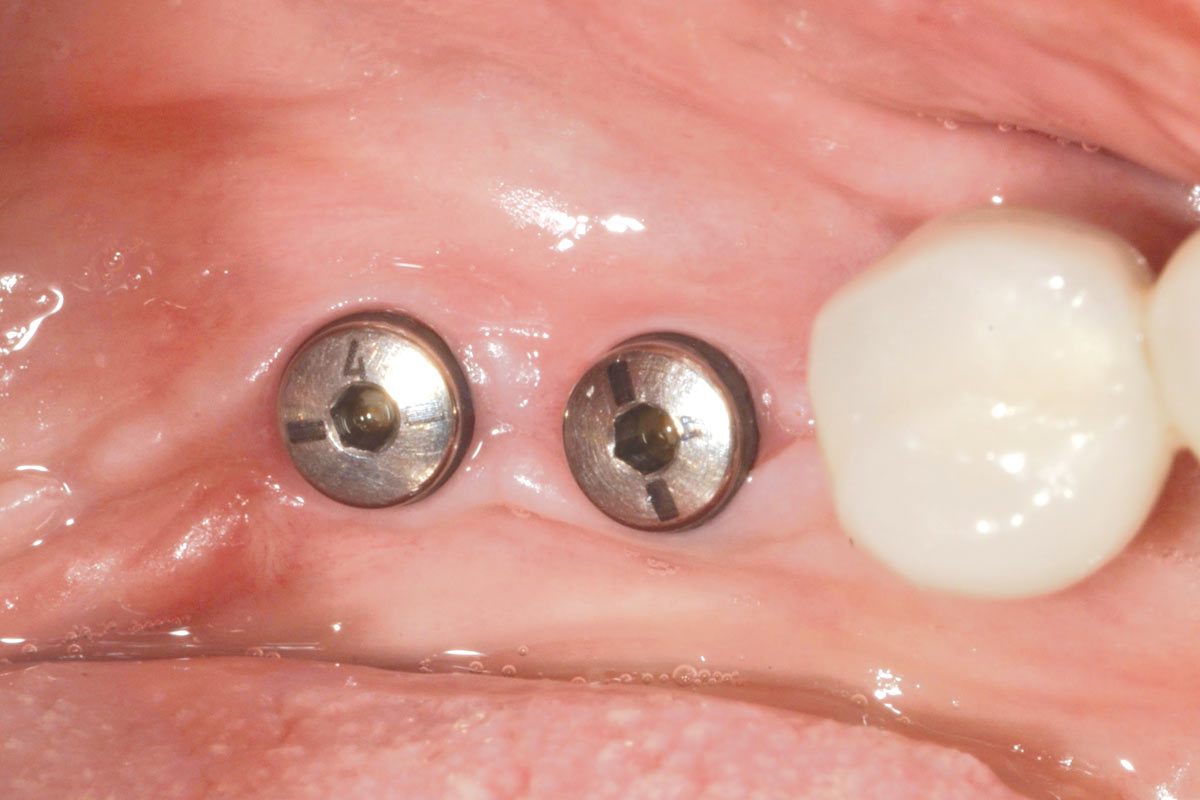

13/16 - Soft tissue profile at 7 weeksPeri-implant soft tissue thickening with mucoderm® - Dr. F. Rojas-Vizcaya

14/16 - Nice soft tissue profile for final restorationPeri-implant soft tissue thickening with mucoderm® - Dr. F. Rojas-Vizcaya